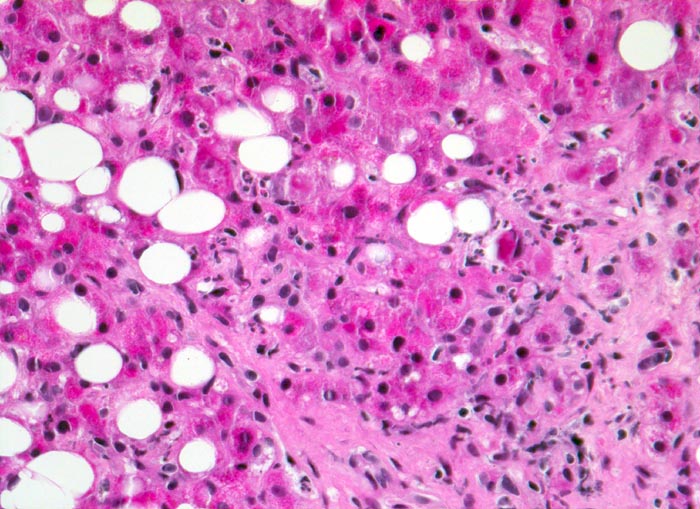

AP/ Floride alkoholische Steatohepatitis

Floride alkoholische Steatohepatitis

Leber